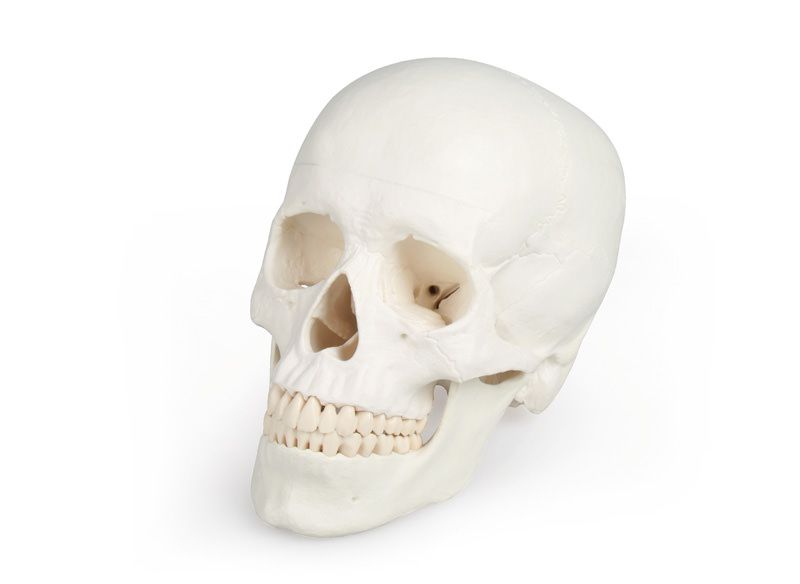

Anatomical model - Human skull in three (3) pieces

Anatomical model - Human skull in three (3) pieces.